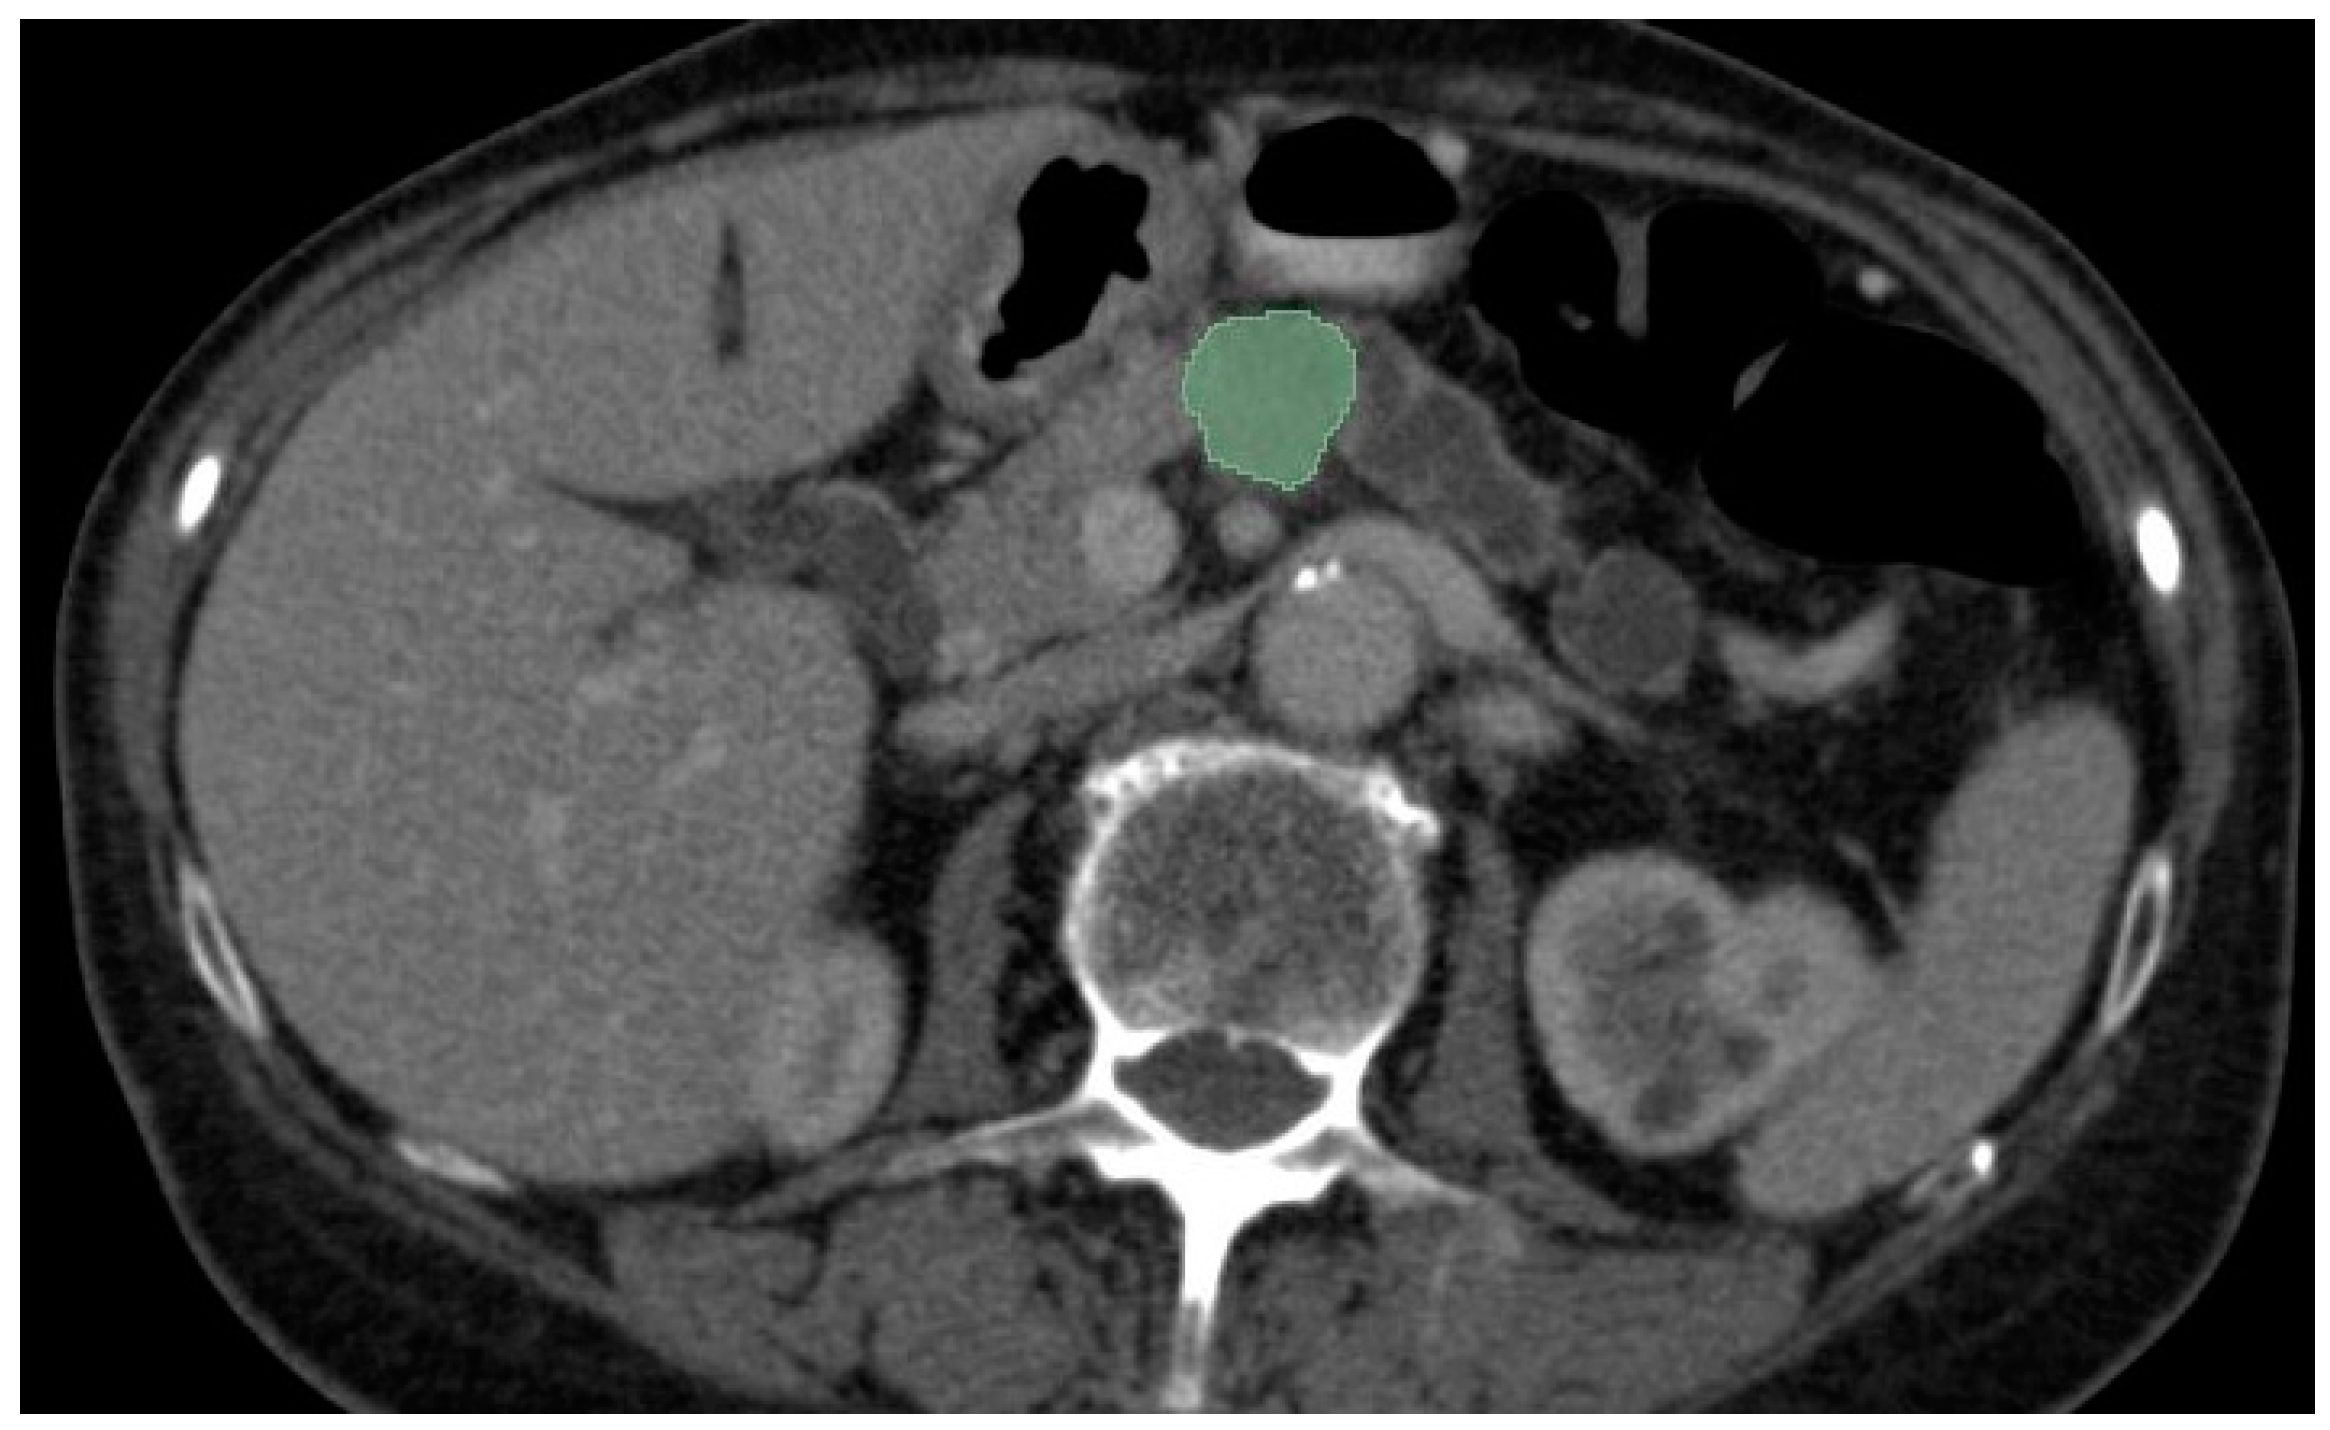

2. Imaging Modalities